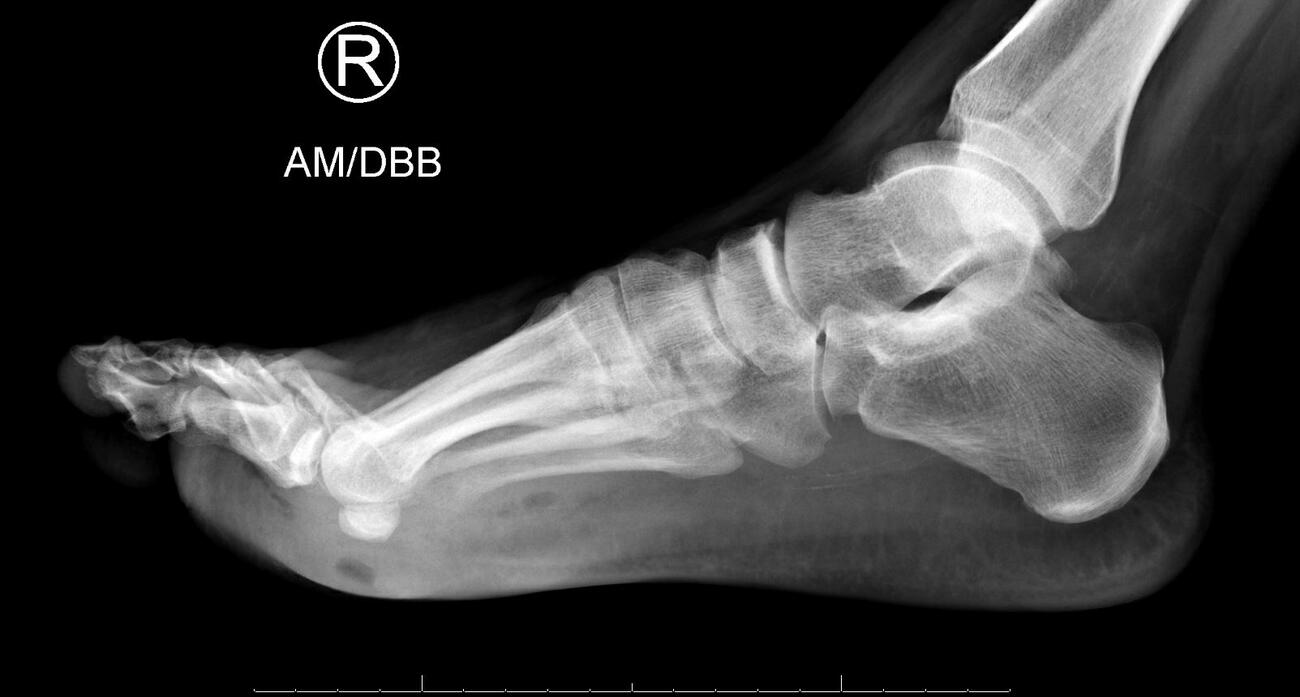

We present an unusual case of a 39-year-old male with poorly controlled type 2 diabetes, and status post-myocardial infarction, who presented to the ED with an infected chronic plantar right foot wound. There was no superficial dermatophytosis noted to the foot. He began empiric IV antibiotics, and a right foot MRI showed osteomyelitis of the bases of the fourth and fifth proximal phalanges as well as the head of the fourth metatarsal. He underwent initial irrigation and debridement of the wound with resection of the infected bone; however, on the first postoperative day he continued to have severe foot edema, erythema, and purulence from the operative foot. Computed tomography (CT) and repeat MRI showed no plantar abscess; however, clinically and intraoperatively noted purulence.